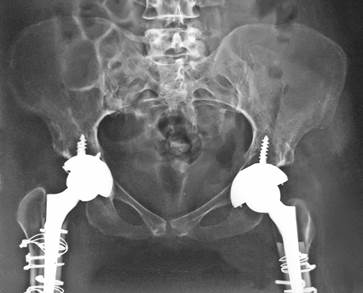

Статья посвящена оценке отдалённых результатов оперативного лечения пациентки с двусторонним врождённым высоким вывихом бедра, которой последовательно выполнены операции эндопротезирования на правом и левом тазобедренных суставах с помощью укорачивающей остеотомии по типу известного финского ортопеда T. Paavilainen и предложенной авторами модификации имплантации бедренного компонента эндопротеза в узкий костномозговой канал. Пятилетний анализ результатов операций показал хорошую функциональную активность обоих искусственных тазобедренных суставов и рентгенологическую стабильность компонентов. Все эти годы пациентка находилась в активном работоспособном состоянии, передвигалась без дополнительной опоры и оценивала свое качество жизни на максимальном уровне, что позволяет рекомендовать применяемую модифицированную методику операции как метод выбора при лечении больных с высоким врожденным вывихом бедра.

В качестве клинического примера выполненной операции ЭП ТБС по методу T. Paavilainen с предложенной авторами модификацией представлена пациентка А., 37 лет, с двусторонним высоким врожденным вывихом бедра. Рост пациентки — 136 см, вес — 48 кг. До операции проводимые курсы консервативного лечения давали кратковременный положительный эффект. В последние 5 лет постепенно нарастали гипотрофия мышц обеих нижних конечностей, затруднения при ходьбе с «утиной» походкой, ограничения движений в ТБС, боли при ходьбе в пояснично-крестцовом отделе позвоночника. После обследования в РНИИТО, учитывая пожелание больной, запланирована высокотехнологичная операция на правом ТБС по методу T. Paavilainen.

При предоперационном планировании на первый взгляд на обзорной рентгенограмме ТБС определялось расположение головки правого бедра в крыле подвздошной кости на 5 см выше истинной вертлужной впадины и сужение бедренного канала, диаметр которого соответствовал минимальным размерам стандартного БК эндопротеза Zimmer Wagner № 13 (диаметр проксимального конца ножки — 14 мм, дистального — 7 мм, длина — 11,4 см), и возможность его применения (рис. 3).

Через 5 лет после операций на контрольных рентгенограммах определяются правильные соотношения компонентов эндопротезов в обоих ТБС (рис. 4). У пациентки полностью отсутствует болевой синдром и отмечены высокие показатели по шкале Харриса — 85 баллов.

Рис. 4. Рентгенограмма таза пациентки А. через 5 лет после операций на тазобедренных суставах по методу T. Paavilainen